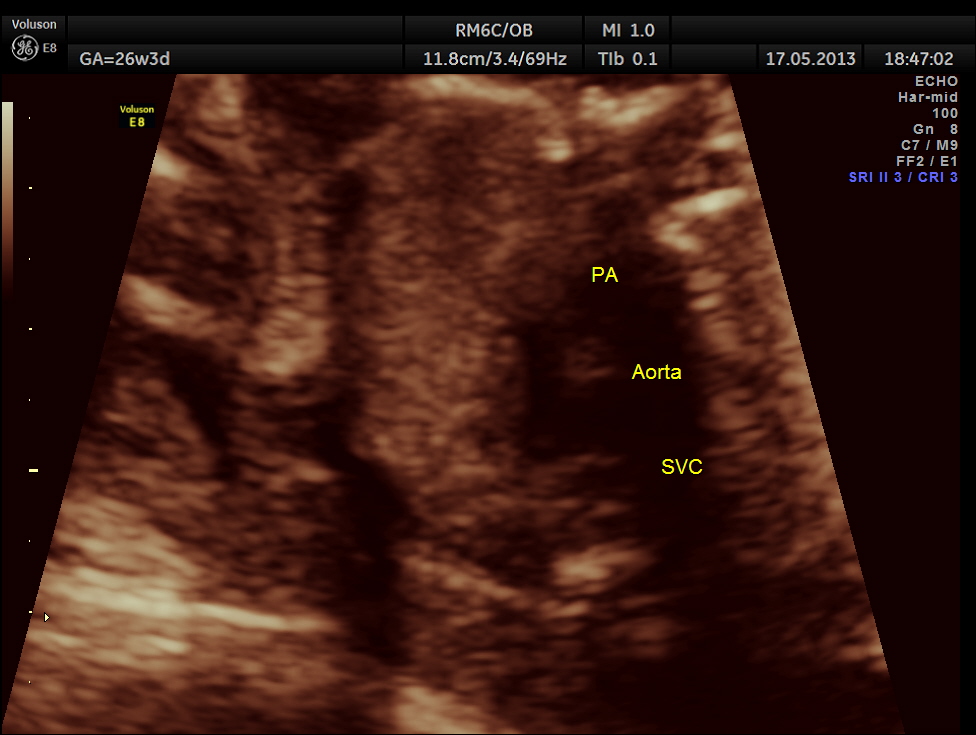

The following images show the sections of the heart.

This fetus did not show any oro-facial clefts ; heart and spine appeared normal.